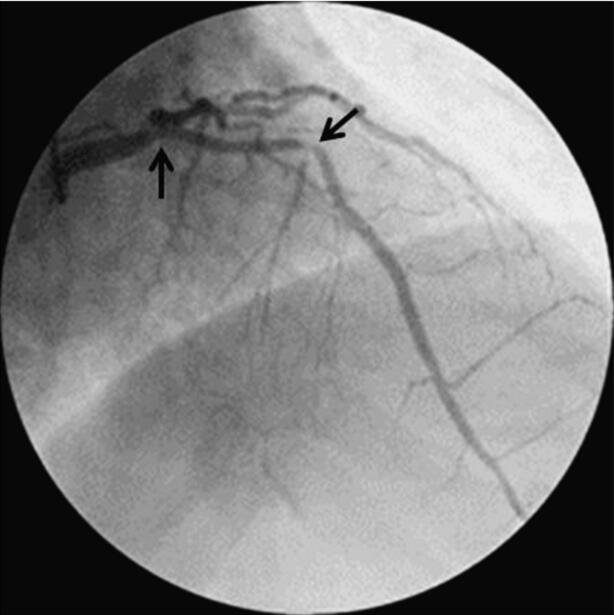

图068‐1 LAO 50°+RAO30°

1月30日冠脉造影示:左主干远段狭窄50%,LAD开口狭窄95%,中段狭窄90%,可见血栓影像;LCX开口狭窄40%,远段节段性狭窄80%;钝缘支近段狭窄70%;RCA开口狭窄70%。患者于1月31日转至胸心外科行左内乳动脉‐前降支旁路移植手术。于2月10日行RCA开口支架置入(图068‐1~图068‐5,病变处标以箭头)。

图068‐2 RAO30°+CRA 20°